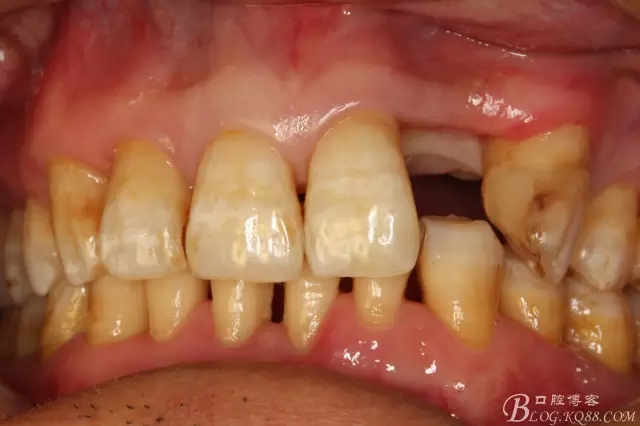

患者、楊xx、男、49歲。主訴:左側(cè)前牙拔除半年,活動義齒修復(fù)四個月,要求種植修復(fù)。專科檢查:21缺失,牙槽粘膜厚度正常。CBCT檢查:高度16mm,寬度7mm.術(shù)前簽知情同意書。

圖3.術(shù)前口內(nèi)照片:正面觀閉口位